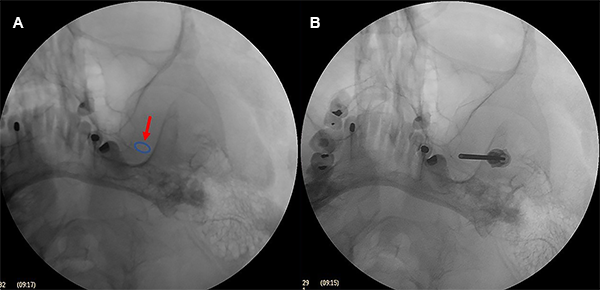

La aguja guiada de los tres puntos referenciales en la hemicara y bajo control fluoroscópico debe dirigirse a un punto en la línea clival 5-10 mm por debajo del piso de la silla turca o en la intersección del peñasco del hueso temporal con el clivus, hasta que se engancha en el agujero oval. Es innecesario penetrar más allá del agujero. La aguja simplemente permanece en el agujero oval (Figura 5).

Cuando es difícil ingresar al foramen oval se puede obtener una imagen en fluoroscopia en incidencia submento-vertical para visualizar el foramen oval; sin embargo, como esta incidencia es difícil de realizar en una cama quirúrgica, se realizó una incidencia fronto-submaxilar oblicua (Figura 6).

Figura 6: Incidencia fronto-submaxilar. El agujero oval izquierdo se ve medial a la rama de la mandíbula y lateral al maxilar sobre el borde del peñasco.

Se retiró el mandril y se introdujo un punzón guía de punta redonda de 13 cm de longitud que atravesó el foramen oval y se hizo el control radiográfico, el punzón facilita la entrada del catéter Fogarty a través del cavum de Meckel. Si hay una resistencia al avance del punzón guía, entonces la aguja no está en la posición correcta.

Se retiró el punzón y se introdujo un catéter Fogarty 4F a través de la luz de la aguja y la punta del catéter debe atravesar 18 mm desde el foramen oval hasta el poro trigeminal.